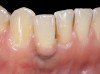

Problem: The implant is placed too facial with significant recession on the midfacial aspect of the abutment and/or crown; the implant is healthy and the patient has a high smile line with an intermediate to thick periodontal phenotype (Figure 1 and Figure 2).17-19

Fig 1. Midfacial recession can affect the esthetics of a smile and lead to an unsatisfactory outcome.

Fig 2. The cause for midfacial recession is excessive labial implant placement. Secondary to poor placement is overcontouring of the implant abutment.